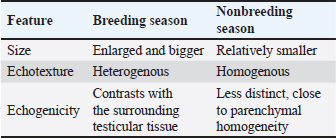

Histological examinationTo study the differences in histological structure during the fluctuations from the breeding season to the non-breeding season, testes were collected at different time points from December to March (breeding season) and from early June to late July (non-breeding season). The testis was divided by dense connective tissue septa into lobules containing seminiferous tubules where the sperms are produced. These tubules were more elongated in the breeding season (Fig. 2a) and round or oval in shape during the non-breeding season (Fig. 2c). The mean diameter of these tubules was larger in the breeding season than in the nonbreeding season, which is statistically insignificant (Fig. 2e). These seminiferous tubules were lined by stratified germinal epithelium composed of several phases, such as round spermatogonia with round dark nuclei, huge primary spermatocytes with enormous spherical nuclei, secondary spermatocytes, and spermatids. Sertoli cells can also be found in seminiferous tubules, which are oval or pyramidal in shape and positioned in the basal portion of the cell with ovoid nuclei (Fig. 2b and d).

Fig. 2. Photomicrograph of H and E stained section of ram testis during breeding season (a and b) and ram testis during non-breeding season (c and d); showing seminiferous tubules “T”, spermatogonium “SP”, primary spermatocytes “Pr”, and sertoli cells “S”. Morphometrical analysis of seminiferous tubule diameters and germinal layer thickness (e and f). Data are presented as mean ± SE. Ns, non-significant; *** highly significant p < 0.001. Histomorphometry revealed a highly significant difference (p < 0.001) in the germinal epithelium thickness between the breeding and non-breeding seasons. The interstitial tissue among the seminiferous tubules contains loose connective tissue and interstitial Leydig cells (Table 5). Table 5. Histomorphometry measurements representing the mean ± SE of seminiferous tubule diameter, germinal layer thickness, number of AR-positive Sertoli cells/tubule area, number of AR-positive myoid cells/tubule area, and number of S100 protein-positive cells per seminiferous tubule.

Immunohistochemical studies showed that the androgen receptor antibody was expressed at the seminiferous tubules, particularly in the sertoli and myoid cells. The reaction was obviously strong in sertoli and myoid cells in the breeding season, in contrast to the non-breeding season, where the intensity of the reaction was intermediate in sertoli cells and very mild to negative in myoid cells (Fig. 3a and c). Statistically, the number of AR-positive Sertoli cells and myoid cells was higher in the breeding season than in the non-breeding season p < 0.05 (Fig. 3e and f). The immunoreaction for S-100 protein revealed strong S-100 expression in Sertoli cells, especially in their nuclei, which appeared darker in the breeding season than in the non-breeding season (Fig. 3b and d). Histomorphometry revealed a highly significant difference (p < 0.001) in the number of S-100-positive Sertoli cells between the breeding and non-breeding seasons (Fig. 3g).